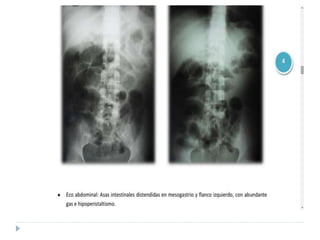

Manifestaciones radiológicas

 Abdomen

 Decúbito lateral

 Hay aire libre por fuera de las asas intestinales y se ubica en el

límite superior, se perciben las sombras retroperitoneales

 De pie

 Íleo paralítico: Hay distensión en el intestino delgado y en el

colón, así como en el estómago. Asas dilatadas con gas en el

colón hasta la ampolla rectal.

 Íleo mecánico: Los niveles HA y la distensión son proximales a

ésta, porque la parte distal se colapsa y el estómago

prontamente se vacía por la frecuencia del vómito.

 PATRÓN DE “U” INVERTIDA

 íleo biliar: Aire dentro de la vía biliar